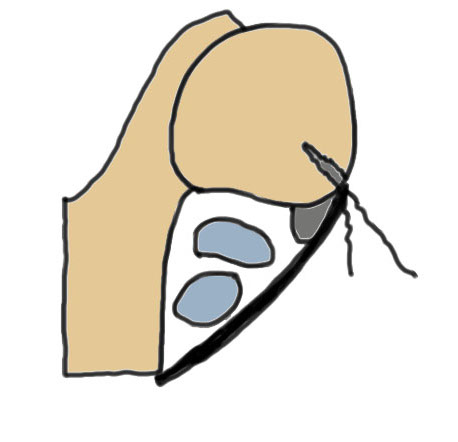

1. Injury to superior peroneal retinaculum (SPR) / fibrocartilaginous ridge (FCR)

Peroneal tendons sublux out of grove

Eckert Classification

| Type 1 | Type 2 | Type 3 | Type 4 |

|---|---|---|---|

| SPR detaches from FCR | SPR and FCR detached | Bony avulsion of SPR and FCR | Midsubstance rupture of SCR |

| 51% | 33% | 13% | ? |

Anterior subluxation of peroneal tendons

Anterior subluxation of peroneal tendons